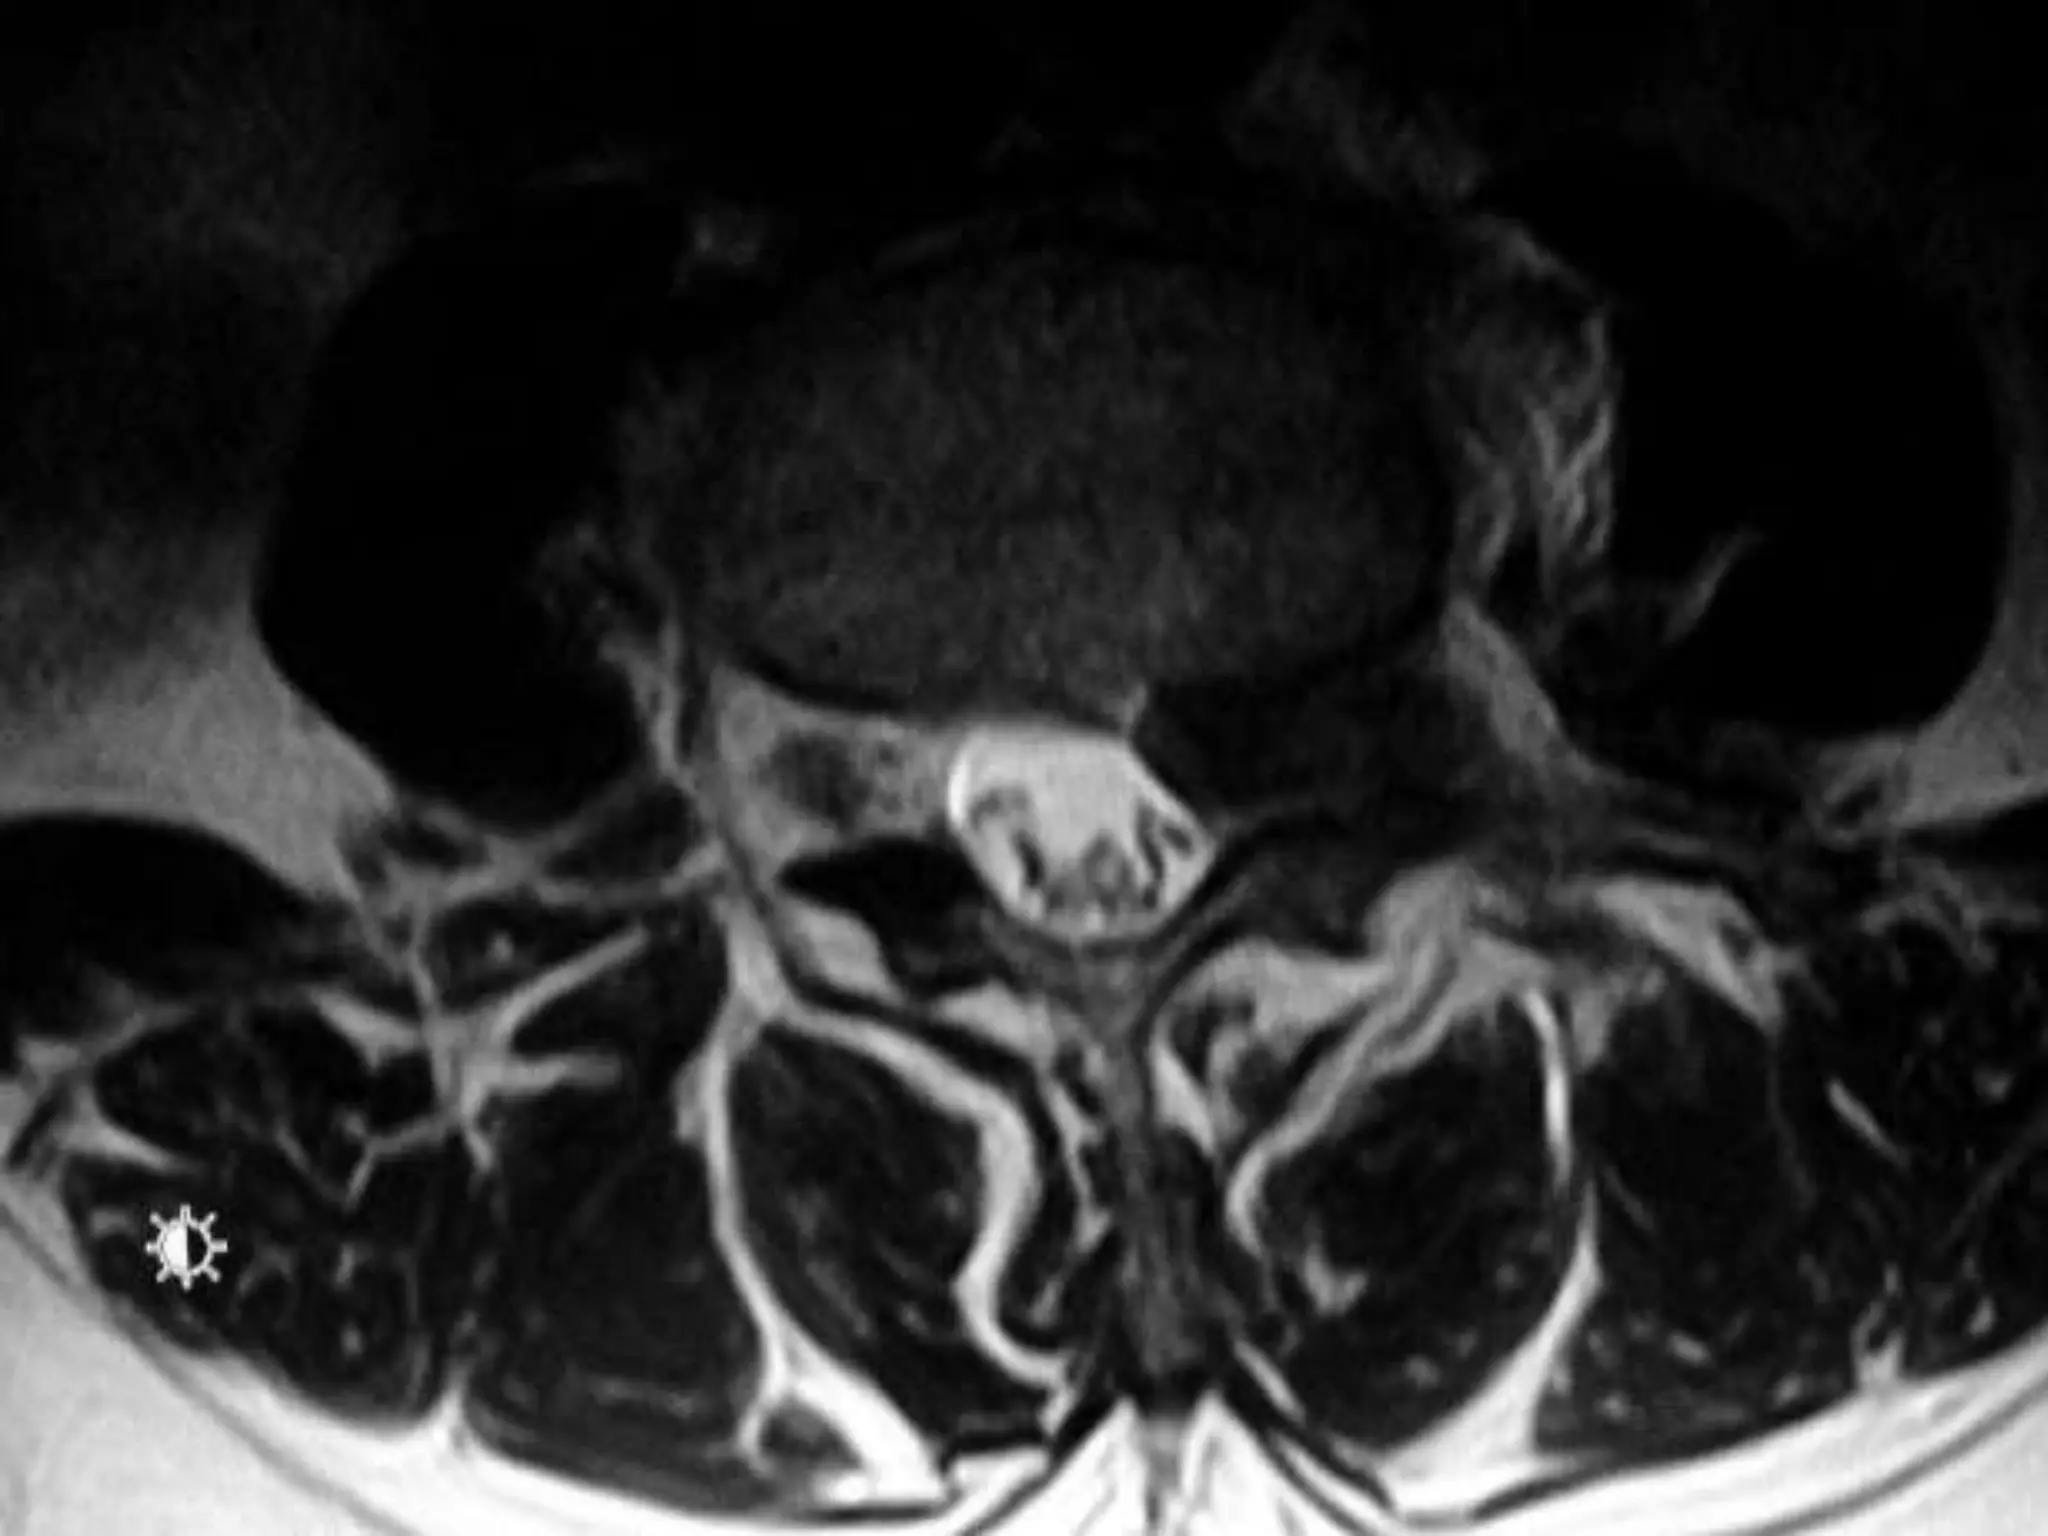

Dynamic Degenerative InstabilityFlexionExtension